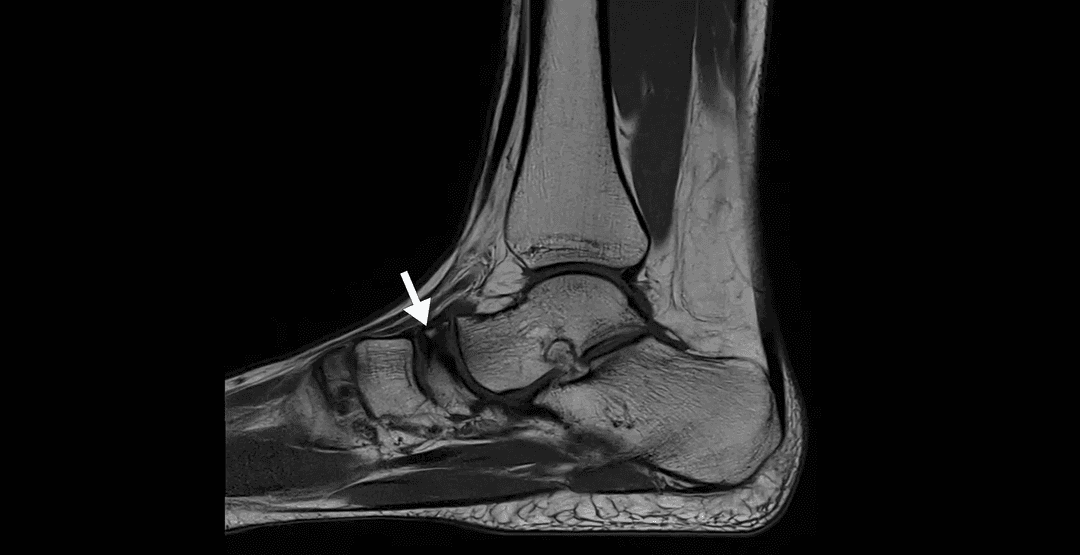

IRM

Description

La maladie de Köhler est une ostéochondrose rare affectant l'os naviculaire du pied chez les enfants. Elle est caractérisée par une nécrose avasculaire transitoire de cet os, conduisant à des douleurs et à des difficultés à marcher. La maladie survient généralement chez les enfants âgés de 3 à 7 ans, avec une prédominance chez les garçons.